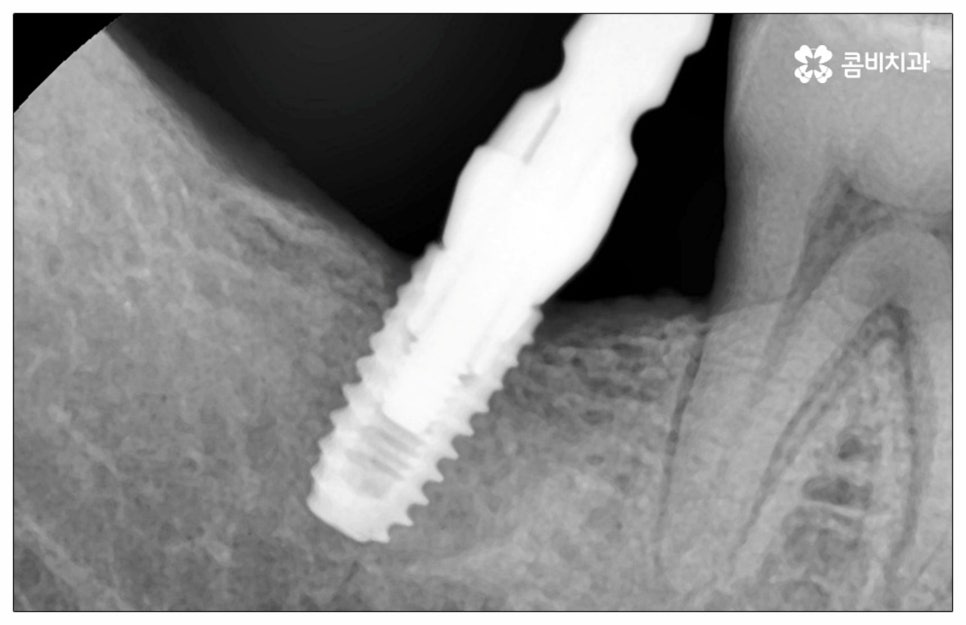

이때 추가 수술은 비급여 항목으로 건강보험임플란트 대상에서 제외되니 이에 대해서도 꼼꼼하게 살펴보시고 정밀 검진 후 담당 의료진과 자신의 상황에 대해서 충분하게 상담해 보시길 권유드리고 있습니다. 추가 수술의 대표적인 예로는 뼈이식 수술이 있는데요. 이것은 임플란트를 식립할 때 바탕이 되는 잇몸뼈의 높이나 폭, 밀도 등이 부족하다면 먼저 이를 보충해 주고 나서 임플란트를 심어주는 과정을 의미하며 같은 이유로 식립 성공률이나 장기적인 안정성을 높이기 위해 꼭 필요한 사전 처치, 즉 상악동 거상술 및 치주 질환 관련 수술 등을 먼저 해야 한다면 이 역시 추가 수술의 범주로 들어가니 자신의 상황에 대해서 상세하게 알아보실 필요가 있어요.